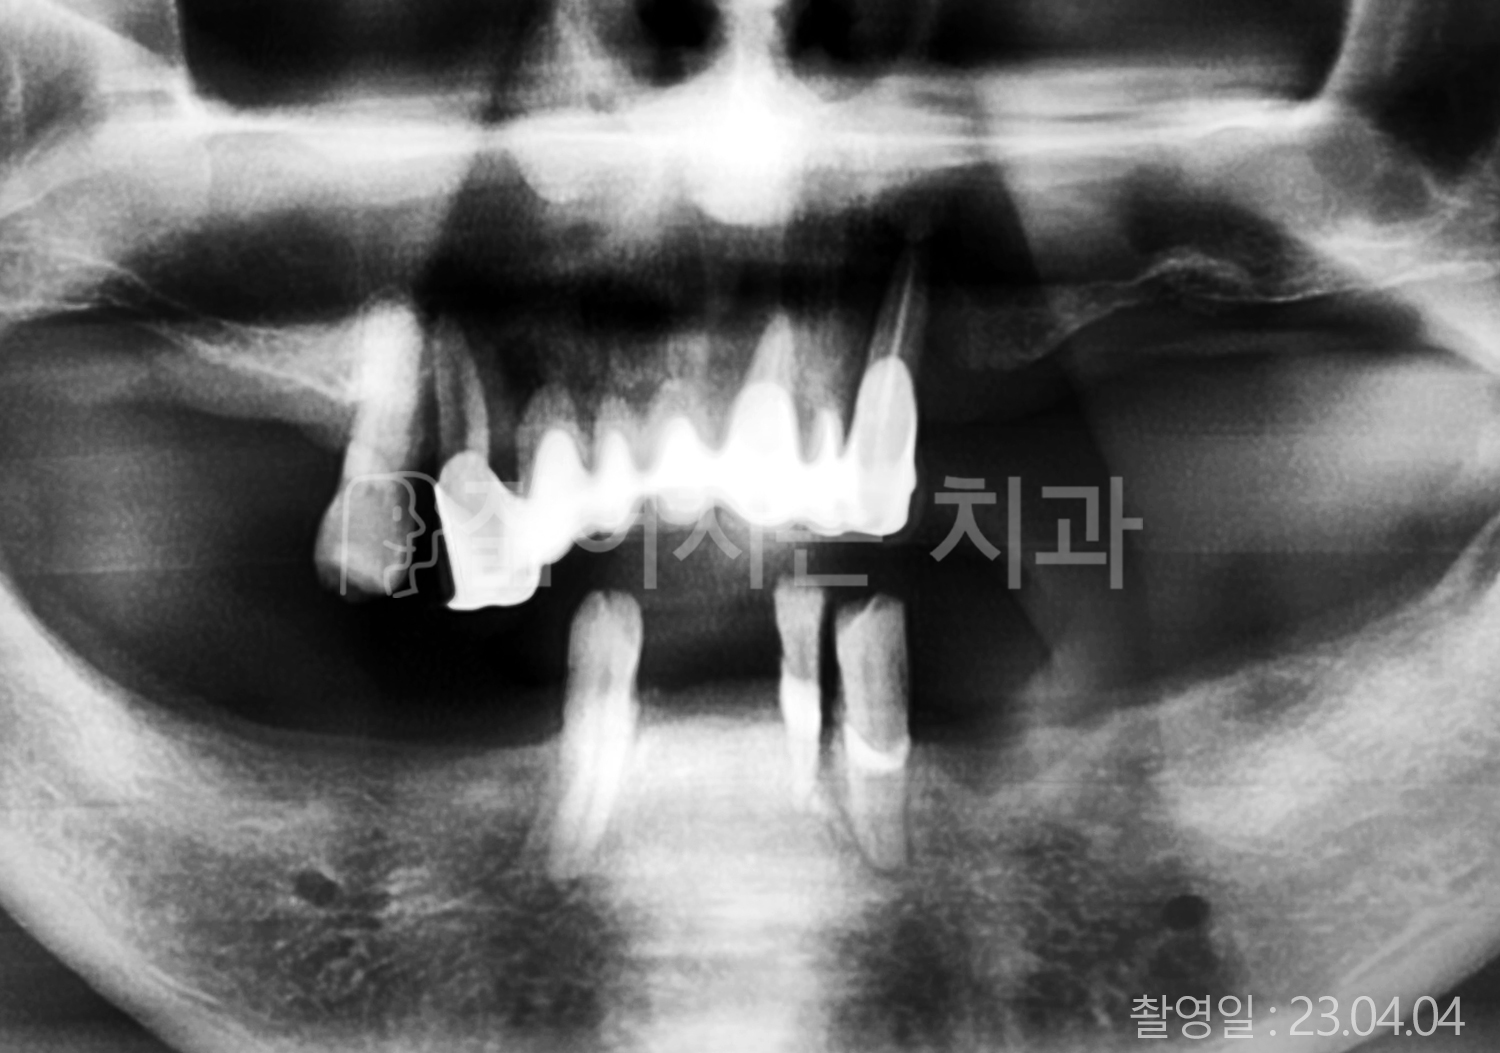

• 40대 전체치아 10개 이상 임플란트

• 50대 전체치아 10개 이상 임플란트

• 50대 고혈압, 당뇨, 고지혈증 전체치아 10개 이상 임플란트